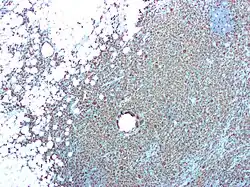

| CD68 immunostaining on this photomicrograph shows macrophages and giant cells in a case of xanthogranulomatous pyelonephritis. | |

Xanthogranulomatous pyelonephritis

Xanthogranulomatous pyelonephritis is an unusual form of chronic pyelonephritis characterized by granulomatous abscess formation, severe kidney destruction, and a clinical picture that may resemble renal cell carcinoma and other inflammatory kidney parenchymal diseases. Most affected individuals present with recurrent fevers and urosepsis, anemia, and a painful kidney mass. Other common manifestations include kidney stones and loss of function of the affected kidney. Bacterial cultures of kidney tissue are almost always positive.[25] Microscopically, there are granulomas and lipid-laden macrophages (hence the term xantho-, which means yellow in ancient Greek). It is found in roughly 20% of specimens from surgically managed cases of pyelonephritis.[10]